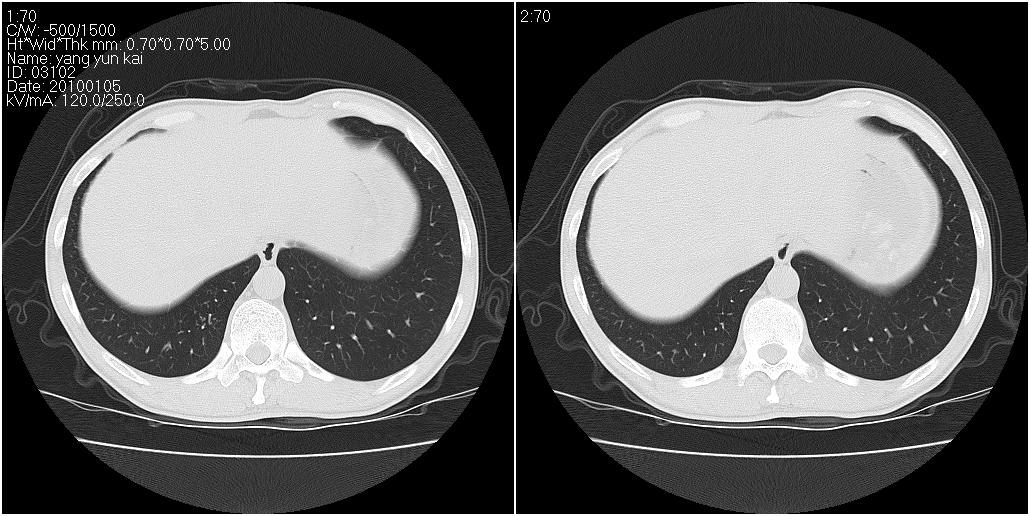

标题: CT23980:男性,47岁。近来咳痰、咳血,血沉增快(40左右),

男性,47岁。近来咳痰、咳血,血沉增快(40左右),痰中未检出结核杆菌。

两肺继发性肺结核并多发性结核球形成,部分病灶内空洞形成。